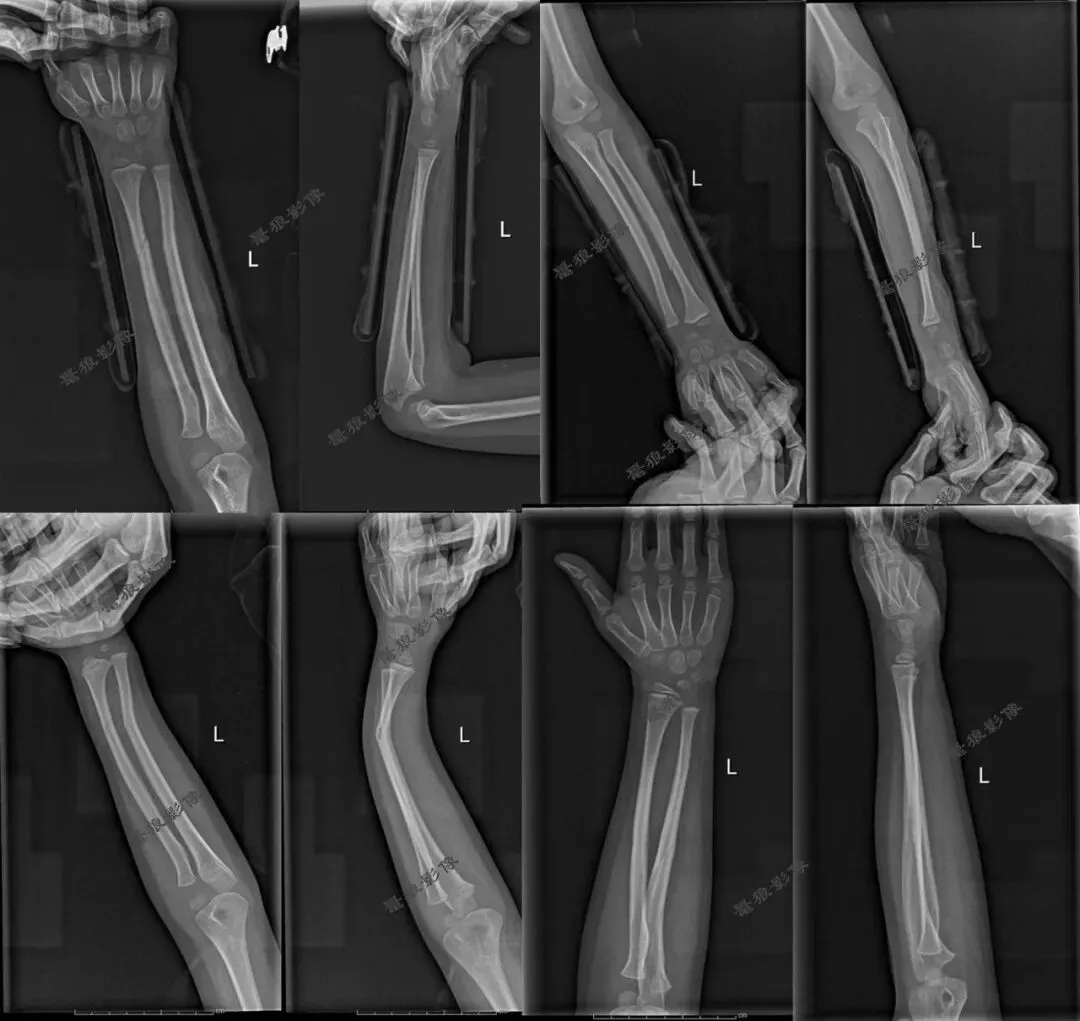

七、需要警惕以下情况发生

三、假如说病人是靠近腕关节那一侧的桡尺骨有问题时,我们拍摄桡尺骨正侧位也只包括一侧腕关节时,这样的拍摄方法(全部伸直或者全部弯曲)也许不会发现此问题。但是病人是肘关节那一侧的桡尺骨有问题时,我们拍摄桡尺骨必须要包括肘关节时,这样的拍摄方法(全部伸直或者全部弯曲)就有问题啦!桡尺骨侧位片伸直显示不出肘关节侧位,桡尺骨正位片弯曲90°显示不出肘关节正位,我们都没法查看肘关节的解剖细节!